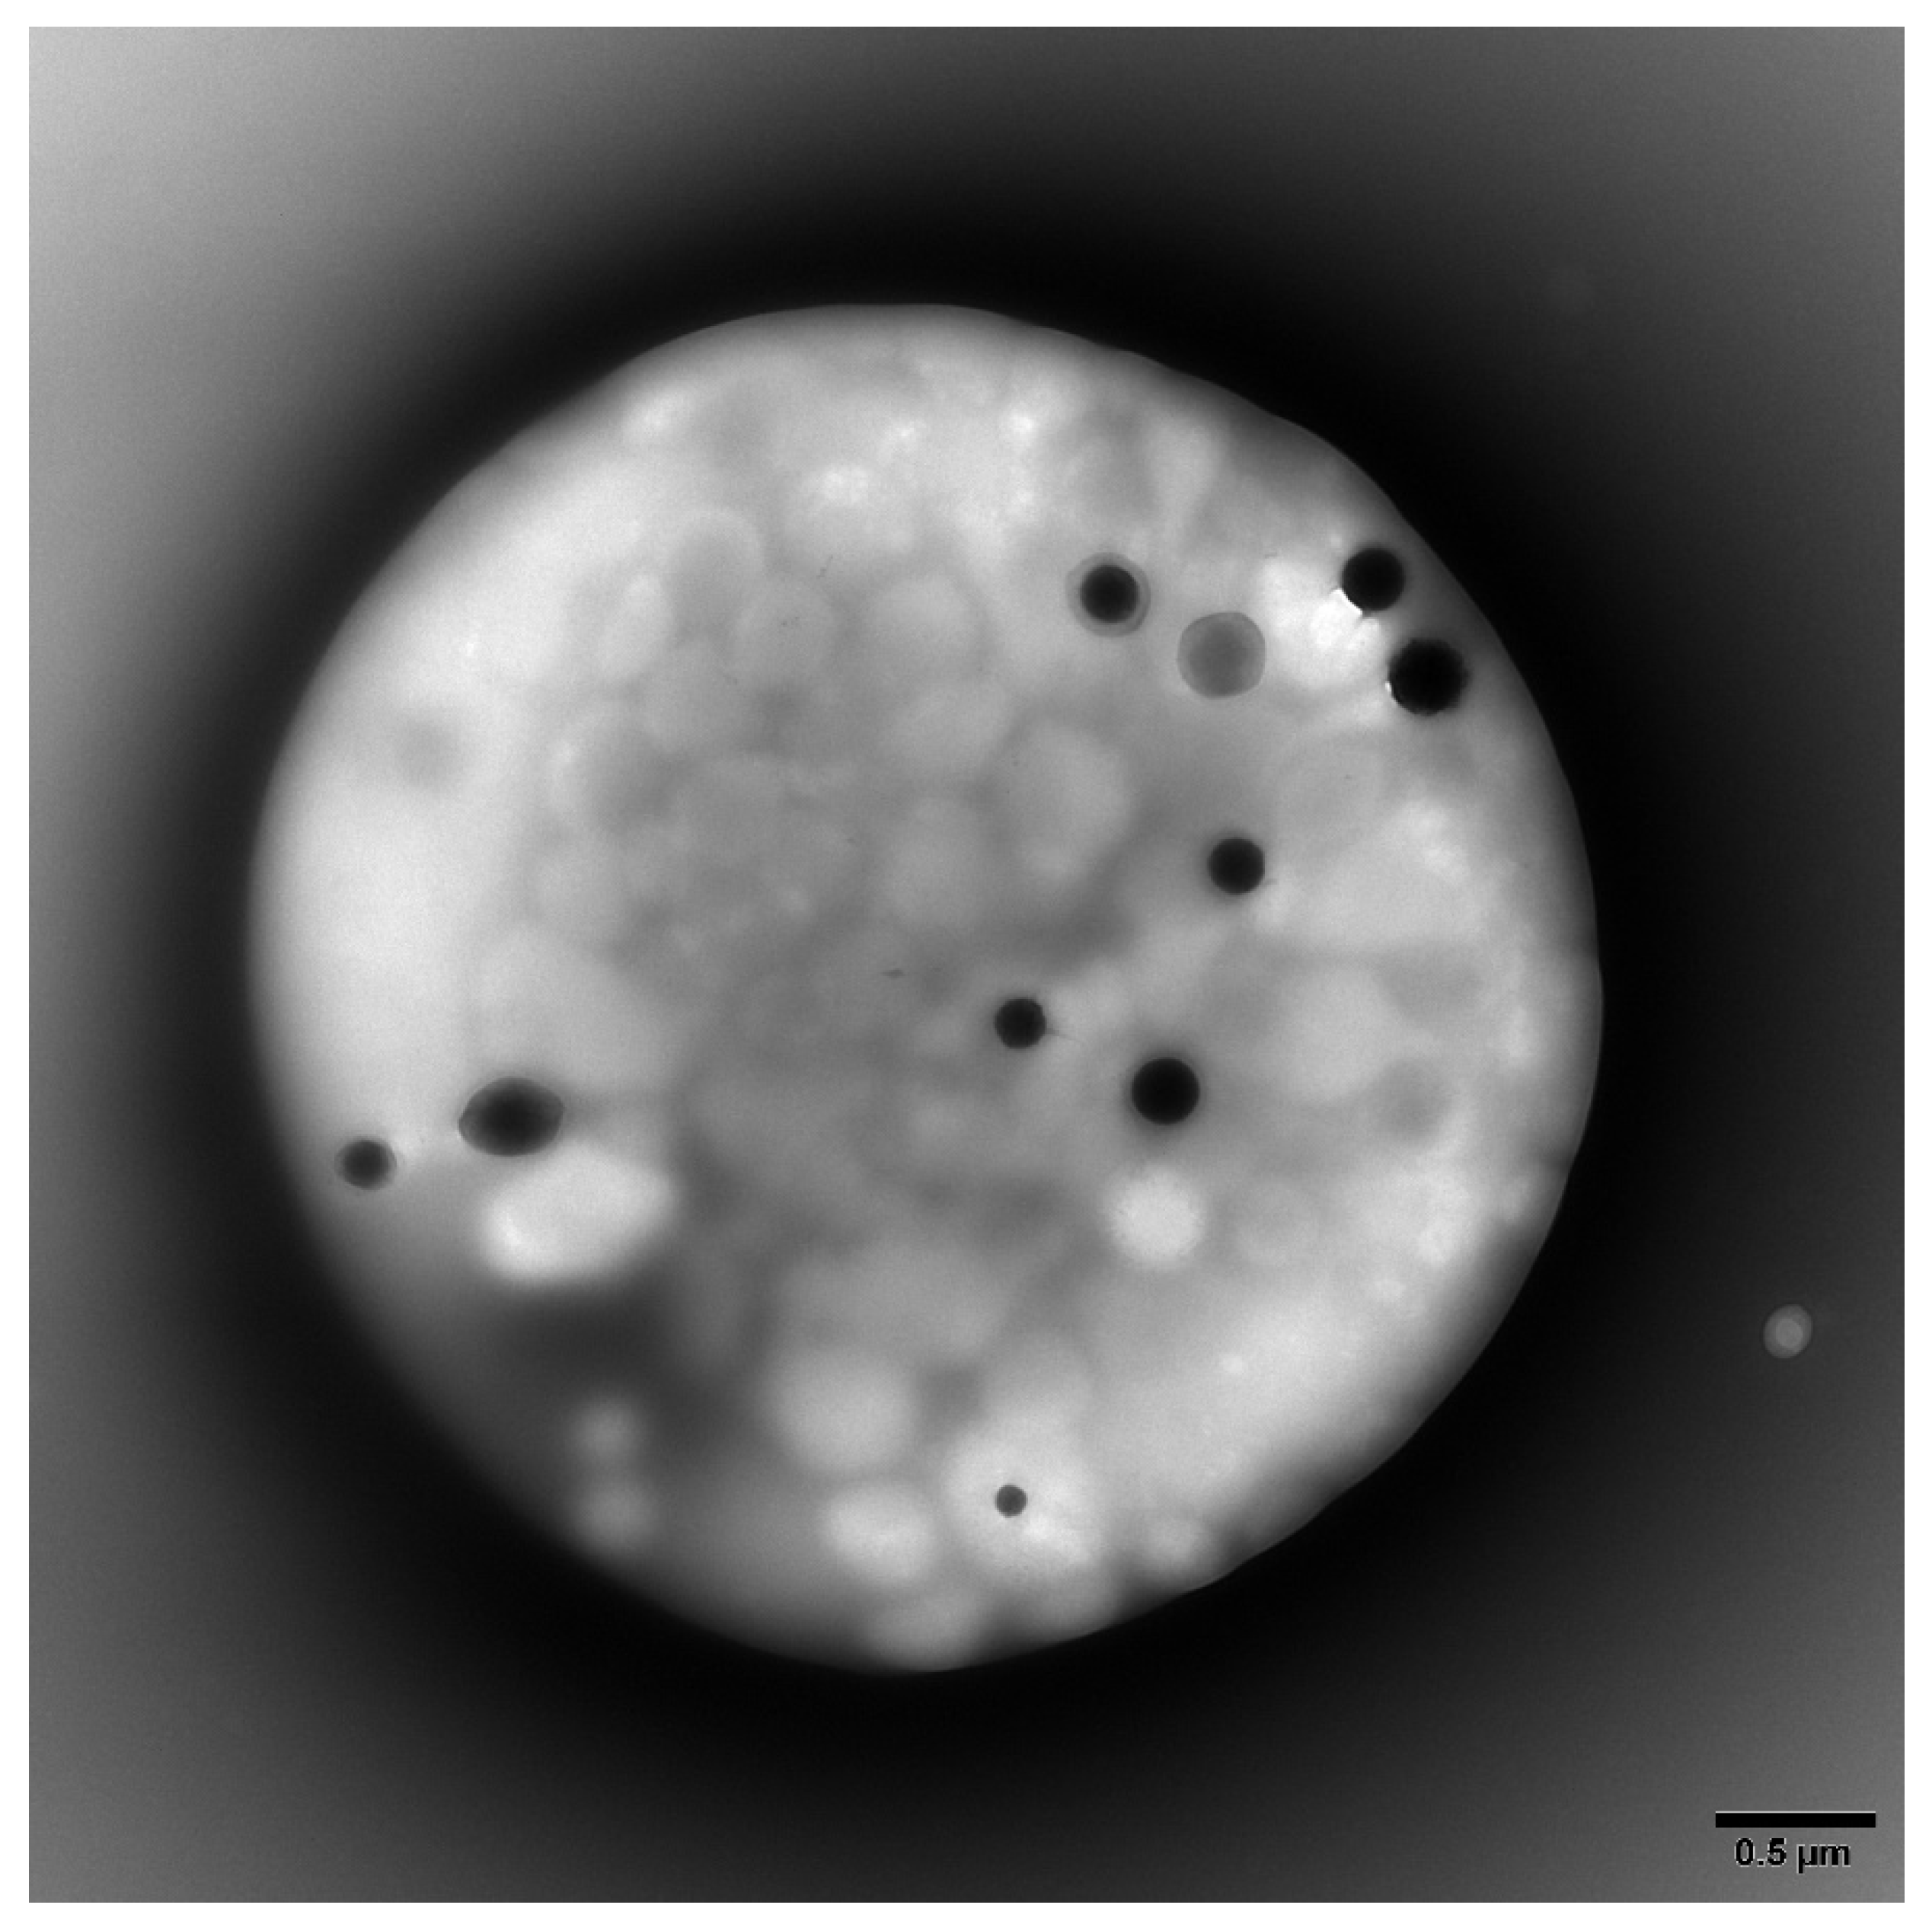

2.2. Platelet Preparations for Electron Microscopy

- Gunning, W.T., 3rd; Karabin, B.L.; Blomquist, T.M.; Grubb, B.P. Postural orthostatic tachycardia syndrome is associated with platelet storage pool deficiency. Medicine 2016, 95, e4849. [Google Scholar] [CrossRef]

- Gunning, W.T., 3rd; Raghavan, M.; Calomeni, E.P.; Turner, J.N.; Roysam, B.; Roysam, S.; Smith, M.R.; Kouides, P.A.; Lachant, N.A. A Morphometric Analysis of Platelet Dense Granules of Patients with Unexplained Bleeding: A New Entity of Delta-Microgranular Storage Pool Deficiency. J. Clin. Med. 2020, 9, 1734. [Google Scholar] [CrossRef]

- Brunet, J.G.; Iyer, J.K.; Badin, M.S.; Graf, L.; Moffat, K.A.; Timleck, M.; Spitzer, E.; Hayward, C.P.M. Electron microscopy examination of platelet whole mount preparations to quantitate platelet dense granule numbers: Implications for diagnosing suspected platelet function disorders due to dense granule deficiency. Int. J. Lab. Hematol. 2018, 40, 400–407. [Google Scholar] [CrossRef]